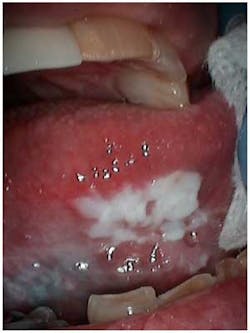

Many seniors are affected by one or more chronic diseases/conditions, which have various oral manifestations; and if the disease itself does not produce an oral manifestation, oftentimes the medication used to treat the disease will. (5) Most dental providers are aware that one of the most common chronic diseases of the elderly, diabetes, results in increased periodontal disease and delayed wound healing. Some may not be aware that enlarged salivary glands/xerostomia and oral candidiasisDental providers must also stay abreast of the many medications prescribed for senior adults treated in their practices, as they typically take several medications to control chronic conditions. The most common oral side effect of medications is xerostomia, which can lead to increased dental caries and periodontal issues. (6) Gingival recession is common among seniors subsequently resulting in an increased potential to develop root caries. The role of the hygienist in assisting the patient with plaque control is of utmost importance and can be quite challenging as many seniors experience decreased mobility and hand-eye coordination. They will need assistance in choosing products for maintaining optimum oral health, requiring different oral hygiene instruction than discussed with younger, more dexterous patients. An interproximal brush may be much more useful than dental floss, or a power toothbrush more effective than manual. Products for alleviating xerostomia may need to be prescribed such as xylitol or pilocarpine, and fluoride varnish may need to be applied to exposed root surfaces.

Oral cancer screenings are important for all patients, but even more so for the geriatric patient, as the majority of oral cancersAs our country experiences this dramatic increase in the older adult population, it would behoove the dental community to learn as much as possible about this complex population. The oral-systemic link has been well documented and will be even more important as we deliver comprehensive oral care to a large population of senior adults in the 21st century.